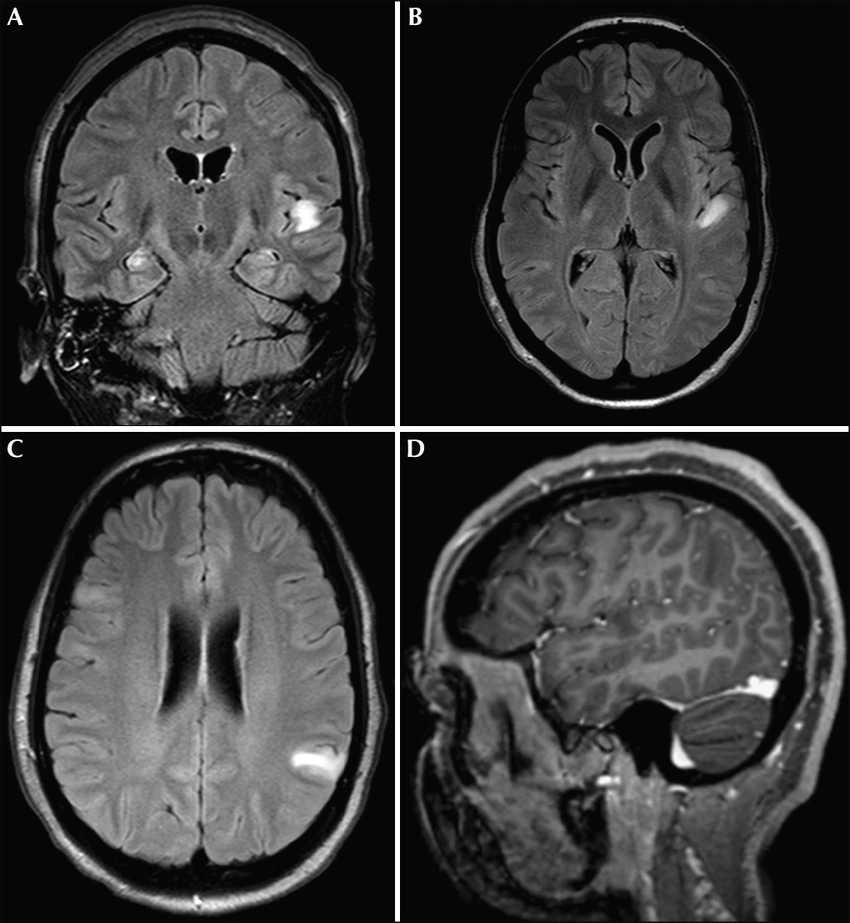

그림 2. 뇌에 생긴 병변의 위치를 신경이미징 방법을 통해 특정한다(Monnerat, 2013). 병변은 정상 세포와는 다른 특성을 가지기에 MRI 를 통해 구분할 수 있다.

인간의 뇌에 있어서도 마찬가지로, 환자들에게는 끔찍한 일이지만 뇌 연구자들에게는 소중한 데이터를 주는 많은 '자연적 파괴' 를 우리는 찾아볼 수 있다. 다른 신체 부위와 마찬가지로 우리의 뇌도 연약한 세포들(심지어 다시 재생할 수 없는) 로 이루어져 있고, 피부나 근육이 상처를 받아 망가지듯이 뇌도 망가질 수 있다. 외상으로 인해 손상을 입을 수도 있고, 다양한 감염이나 염증은 신경세포를 죽이며, 뇌세포에 영양분을 공급해주는 혈관이 혈전으로 인해 막히거나 터질 경우 특정한 지역에 국한된 손상이 일어날 수 있다(그림 2). 이처럼 자연은 다양한 '자연적 실험 사례' 를 의사와 학자들에게 제공해 왔으며, 자연이 끊어낸 전선들은 뇌의 다양한 부위들이 각기 다른 심리적 기능들을 맡는 분업화된 모듈임을 알려 주는 증거가 되어 왔다(미주 1).